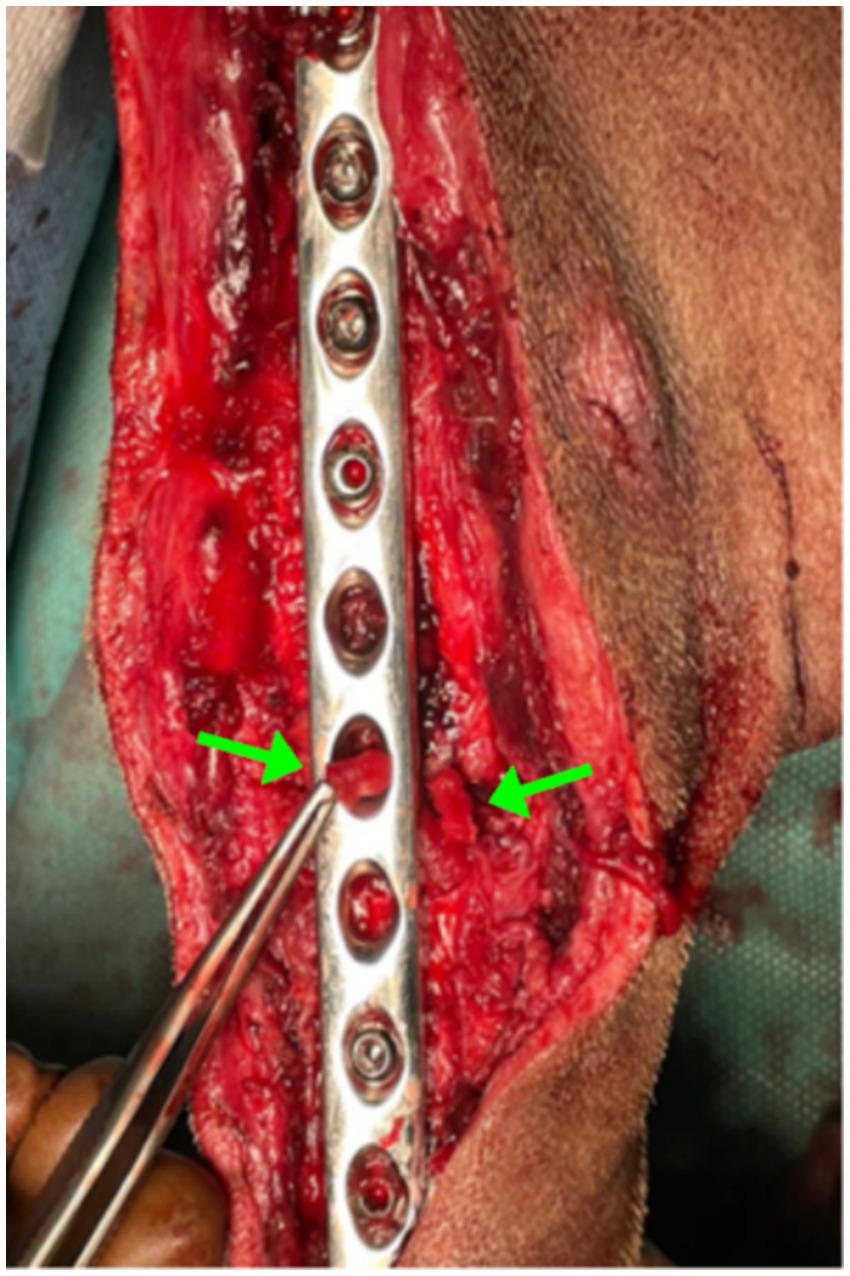

The surgical procedure was performed under general anesthesia. Methadone (0.2 mg/kg IM; Insistor 10 mg/mL, Richter Pharma, Wels, Austria) was administered as premedication, followed 20 min later by dexmedetomidine (0.02 mg/kg IV; Sedadex 0.5 mg/mL, Le Vet Beheer, Oudewater, Netherlands) and ketamine (2 mg/kg IV; Narkamon Bio 10%, Bioveta, Ivanovice na Hane, Czech Republic). Induction of anesthesia was performed with propofol to effect IV and maintained with isoflurane (Isoflutek 1,000 mg/g, Laboratorios Karizoo S.A., Barcelona, Spain) delivered in 70% oxygen. Cefotaxime 25 mg/kg IV (Cefotax 1 g, The Egyptian International Pharmaceutical Industries Company, Egypt) and robenacoxib 2 mg/kg SC (Onsior 20 mg, Elanco GmbH, Bad Homburg vor der Höhe, Germany) were administered 30 min before starting the surgery. Dorsal recumbency was the position, and the affected hindlimb was aseptically prepared for surgery. The shaft of the tibia was approached through a medial incision of the skin. The proximal landmarks were the medial tibial condyle, the midline of the tibia midshaft, and distally to end near the medial malleolus. The subcutis was incised on the same line. The crural fascia was incised along the cranial border of the cranial tibial muscle, starting at the tibial tuberosity and extending distally to the tendinous portion of the muscle. The implants were removed, and samples were collected for microbiological examination, including both biological tissues and parts of the implants. The area was irrigated with a sterile saline solution. At the level of the vicious callus fracture site, an osteotomy was performed with an oscillating saw (18.5 mm × 9.0 mm × 0.48 mm blade) and refracture, removal of the exuberant fibrous callus with the rongeur bone, and realignment of the bone ends. The implants used consisted of a 2.0-mm Kirschner wire intramedullary pin, a 10-hole, 3.5-mm stainless steel LC-DCP plate (limit contact-dynamic compression plate), and 7 self-tapping 3.5-mm stainless steel cortical screws to fix the plate, the length of which depends on the measurements taken intraoperatively with the help of the guide. The space of the osteotomy gap was filled with Alg-Pll-BGAuSP (Figure 2). The crural fascia was closed with 2–0 absorbable monofilament suture in a simple continuous pattern with polydioxanone. The skin was closed with 2–0 non-absorbable synthetic monofilament in a cruciate interrupted pattern with nylon.

Figure 2. Intraoperative image showing the Alg-Pll-BGAuSP composite inserted into the fracture gap. The green arrows indicate the biomaterial within the defect site.